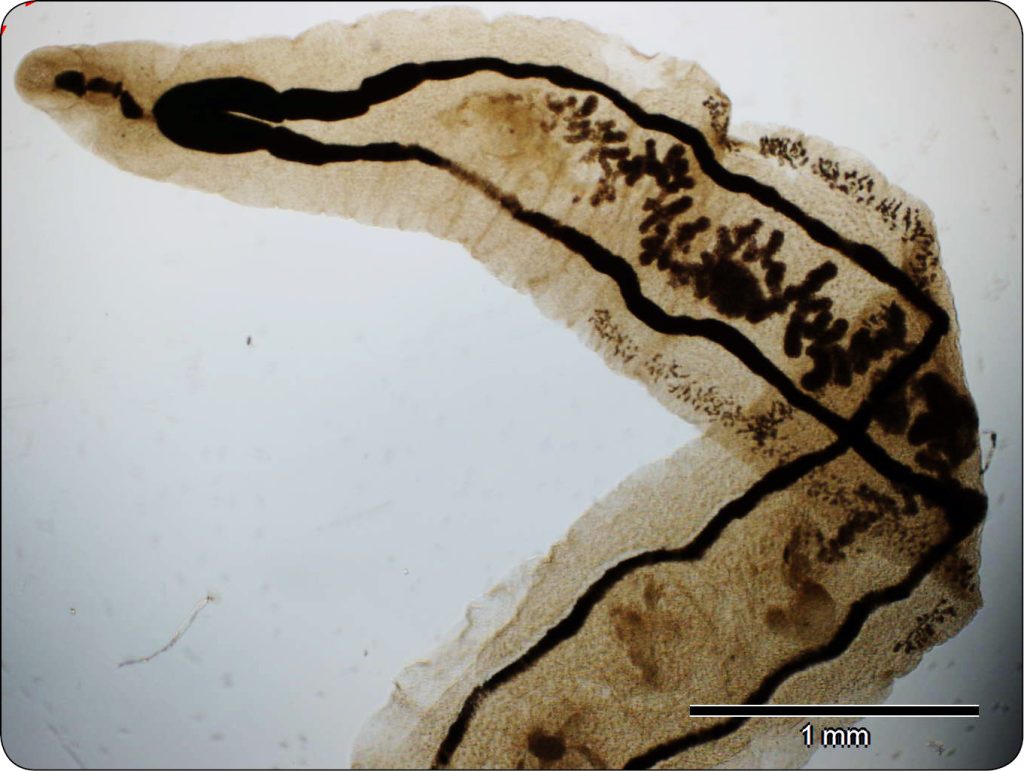

Przenoszona drogą pokarmową przywra kocia – Opisthorchis felineus wraz z dwoma pokrewnymi, azjatyckimi gatunkami: Opisthorchis viverrini i Clonorchis sinensis, należy do triady przywr wątrobowych występujących u psów i kotów. Wszystkie wymienione gatunki mają duże znaczenie zoonotyczne i epidemiologiczne z szacowanymi ponad 40 milionami zakażonych osób w Azji i Europie. Rodzaj Opisthorchis klasyfikuje cztery gatunki: O. felineus, O. viverrini oraz dwa rzadziej występujące Opisthorchis noverca i Opisthorchis guayaquilensis. Wszyscy przedstawiciele taksonu lokalizują się w przewodach żółciowych, sporadycznie w pęcherzyku żółciowym. Są to małych rozmiarów, wydłużone, lancetowate przywry, których dorosłe postaci osiągają rozmiar 1,2-3 x 8-13 mm (ryc. 5). Ludzie i zwierzęta zarażają się poprzez spożywanie surowych, zakażonych ryb słodkowodnych głównie z rodziny karpiowatych – Cyprinidae. O. felineus jest pasożytem, który występuje w Europie i Azji na rozległym terytorium, obejmującym Rosję, Kazachstan i kilka krajów europejskich. Informacje na temat zakażeń O. felineus pochodzą głównie z krajów Europy Wschodniej, tj. Białorusi, Ukrainy i Rosji, a w szczególności z Syberii, gdzie pasożyt ten jest wysoce endemiczny zarówno dla zwierząt, jak i ludzi. W krajach Unii Europejskiej opistorchozę potwierdzono w: Niemczech, Grecji, Litwie, Polsce, Rumunii i Hiszpanii i we Włoszech (1, 2, 4, 7).